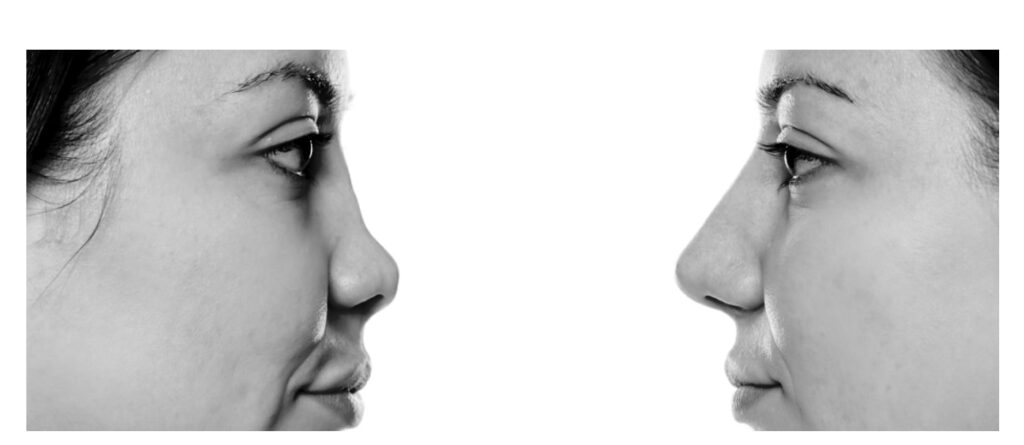

Many people want to make their faces more beautiful with rhinoplasty, but many problems and concerns overwhelm them:

In general, the purpose of cosmetic nose surgery is to correct the size and shape of the nose according to other elements of the face. Also, eliminating nasal defects and maintaining its positive points can lead to a successful nose surgery with the least pain and difficulty. Also, paying attention to the passage of air and observing the principles of surgery that do not cause problems in your breathing or even solve your breathing problems, is another goal of rhinoplasty.

It should be noted that achieving a standard shape and size is based on aesthetic criteria. It means that your surgeon is trying to match the final size of your nose and its angles to other parts of the face and the distances available. Aesthetic criteria will make your nose and face more beautiful in the public eye.